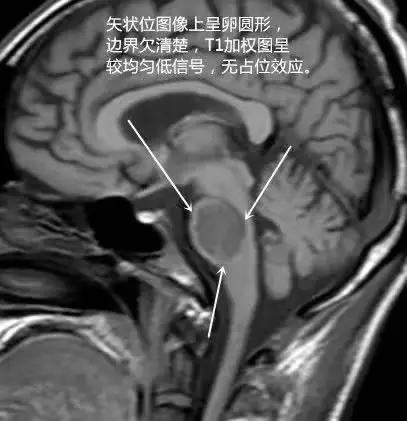

T1 呈低信号,T2 呈高信号,病灶仅累及桥脑中央区,而边缘部分不受累,病灶前方和侧方仅存一薄层脑组织未受累,病灶后缘可延伸到被盖的腹侧。增强后一般无强化,但也可出现强化。

MRI 病变横切位上形态为原形或蝴蝶形,矢状位呈卵圆形,冠状位上呈蝙蝠翼状。